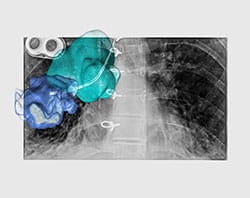

Imaging can be performed in the hybrid OR just before the surgery to help plan the procedure, during the surgery to identify important anatomy or disease, and after the surgery to evaluate results. In some situations, the surgeon will pull up images taken prior to surgery and overlay them with images taken in the hybrid OR. This can provide important details and help improve safety and accuracy.

In addition, the technology can help surgeons see their surgical tools as they navigate them inside the patient’s body. This improves surgical accuracy and helps surgeons avoid critical structures.